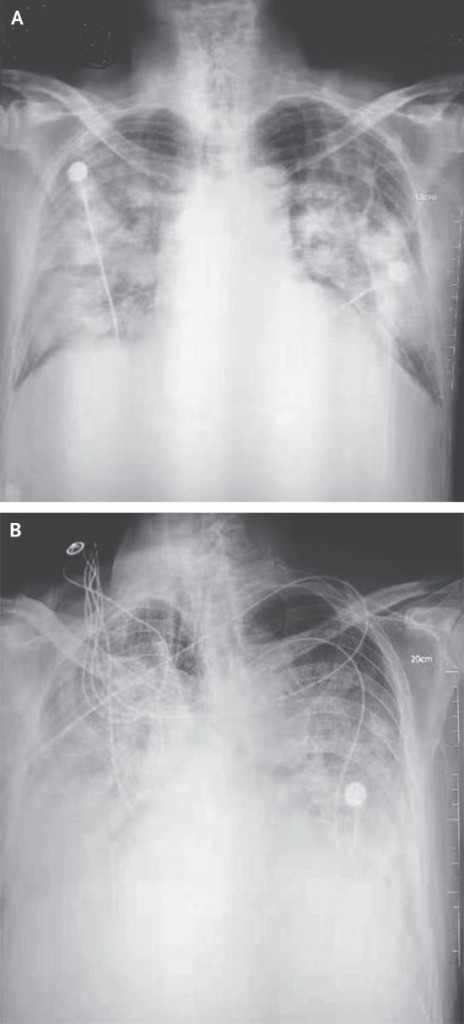

The AI system identifies five key abnormalities: nodules, consolidation, interstitial markings, pleural effusion, and pneumothorax. When a patient undergoes a standard chest X-ray, the AI algorithm analyzes the image and flags any abnormal findings, indicating their location to aid physician review.

Chest X-rays of patients with Wuhan pneumonia.

(Image courtesy of the New England Journal of Medicine )